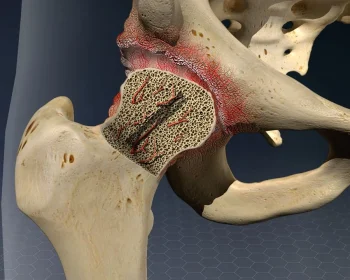

Core decompression osteotomy around the hip is a procedure to relieve pressure within the hip bone, improving blood flow and slowing progression of avascular necrosis.